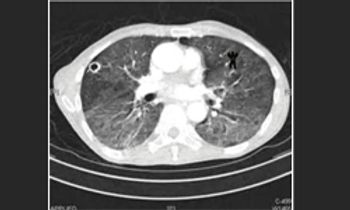

To make a diagnosis of lung cancer, radiologists, who must read radiographs accurately can fall victim to a psychological phenomenon known as inattentional blindness.